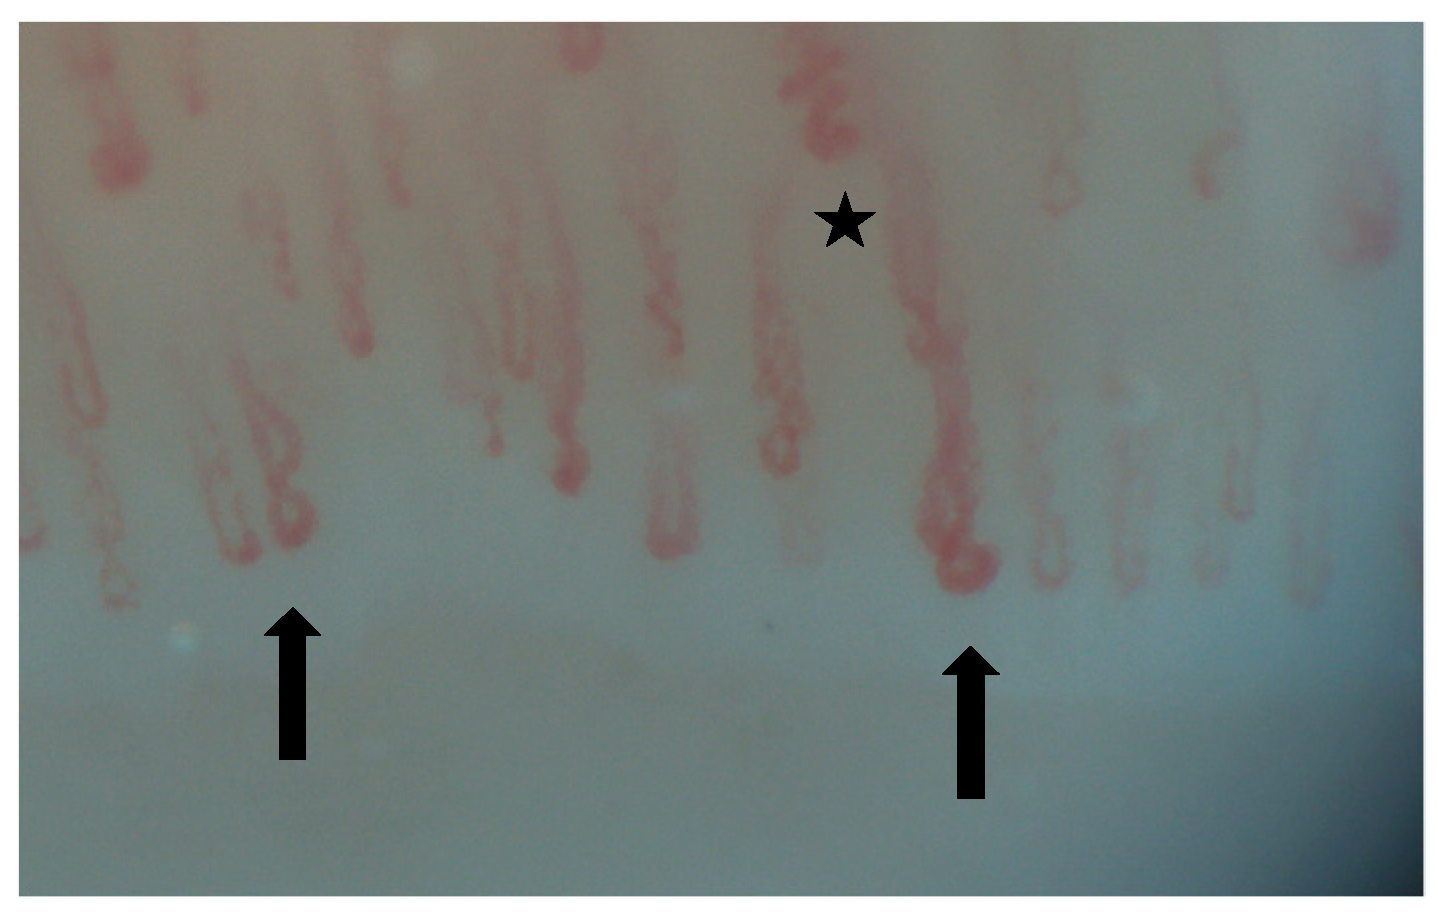

2. Normal Capillary Pattern